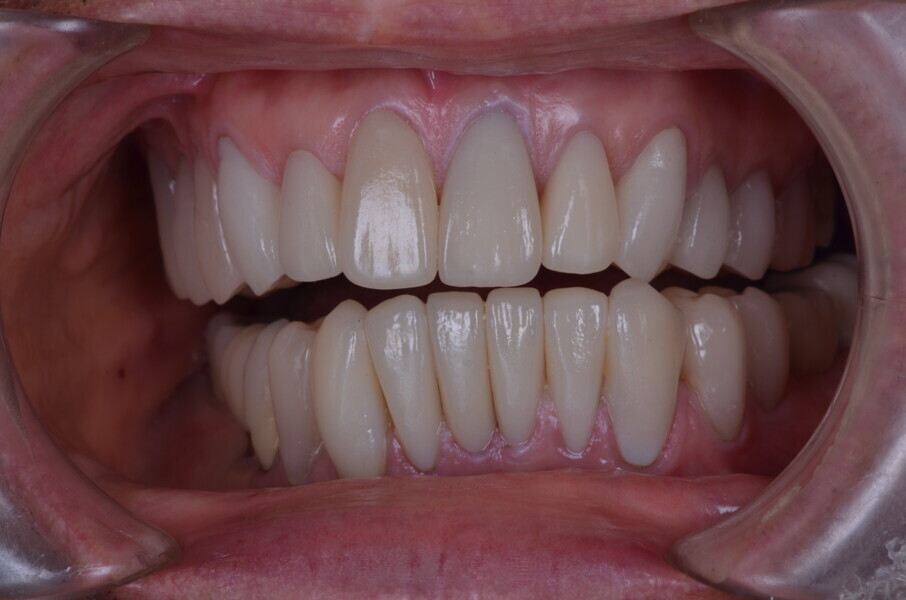

Figure 26 Closed mouth post op